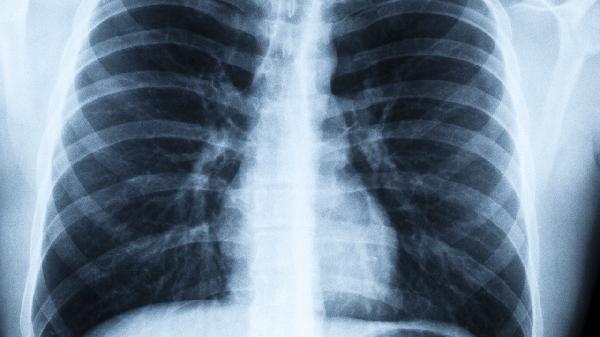

病毒性肺炎恢复期需持续监测体温和血氧变化,建议每日进行呼吸功能锻炼如缩唇呼吸。饮食宜少食多餐,优先选择富含优质蛋白的鱼肉、豆制品,搭配新鲜果蔬补充维生素。保持居室通风换气,湿度维持在50%-60%有利于呼吸道修复。康复后2周内避免人群聚集场所,定期复查胸部影像学评估肺部病灶吸收情况。出现持续低热、活动后气促等症状应及时复诊。